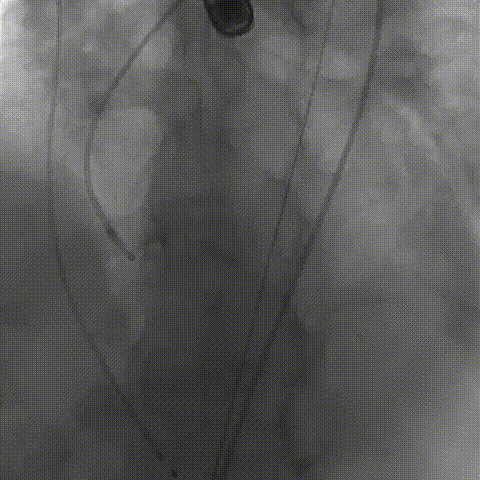

初次释放,无冠窦畸形猪尾难以到达窦底,定位带来挑战;释放至工作位,瓣膜(AV29)位置偏低

瓣膜(AV29)完全回收后重新定位释放

瓣膜(AV29)工作位正交体位造影位置良好,左冠显影正常

瓣膜(AV29)完全脱钩释放后23mm球囊充分后扩,冠脉灌注良好